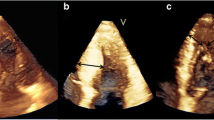

Measurements of PMs obtained from 3DE are presented in Table 3. The total ALPM and total PPM CSA were significantly larger in patients with HC than in controls (1.92 ± 0.81 vs. 1.15 ± 0.47 cm2; p = 0.001 and 1.46 ± 0.62 vs. 1.08 ± 0.37 cm2; p = 0.031, respectively). Figure 1 demonstrates an example of the 3DE analysis of the PM area. There was no significant difference in the number of ALPMs and PPMs between patients with HC and controls. Moreover, bifid and accessory PMs were not observed more frequently in patients with HC than in controls. Figure 2 shows an example of a patient with HC and a bifid PM, and Fig. 3 demonstrates an example of an accessory PM visualized by 3DE.